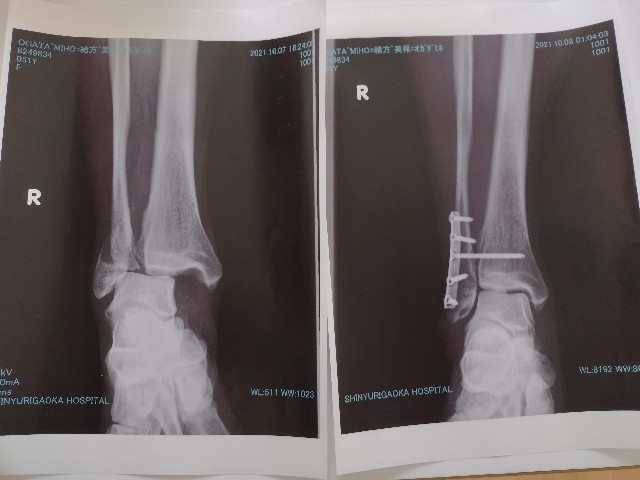

皆さんに大迷惑をおかけした「腓骨骨折」が10月7日。

あの時は自分の脛骨を目の当たりにし、「足首が崩壊した~」と目の前が真っ暗だったなぁ。

一年が経過し、診察も終了。

痛みや違和感はあるものの、先生からも「何をやっても良い」と言われました!(^^)!

振り返ってみると骨折してしまったのはダメダメだったけど、運ばれた病院も外傷再建センターという専門医がいる病院だったし、私自身健康で手術や傷の管理でトラブルもなかったし、ケガをしたところ以外はしっかり動かせる体力もあったし…。